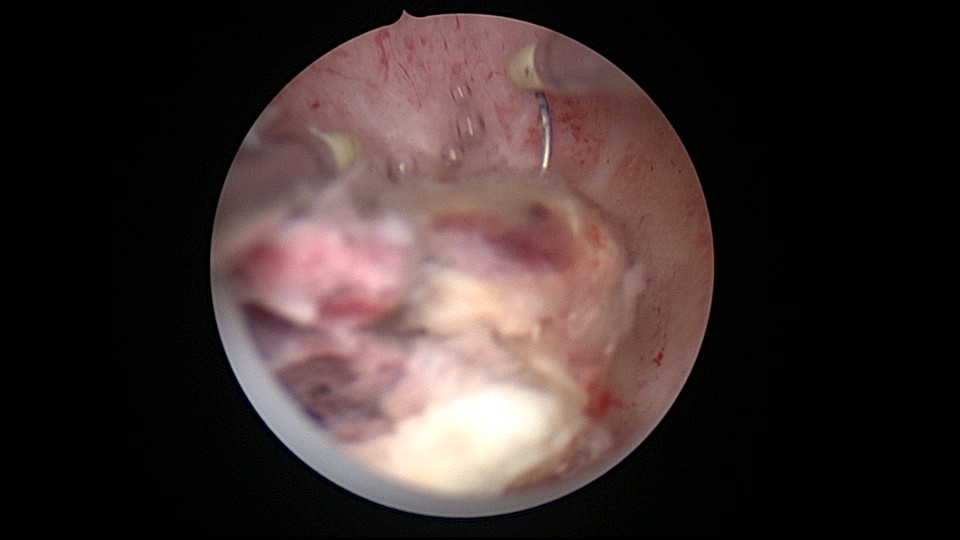

患者25岁,G1P0,停经52天,稽留流产,B超宫内偏右查见大小约2.4cmx1.0cmx1.7cm孕囊回声,形态规则,内可见直径约0.4cm的卵黄囊回声,未见胎芽,孕囊旁肌层最薄处厚约0.5cm,子宫中下段回声连续性欠佳,似可见一分隔回声。2021年7月宫腔镜探查,胚胎着床于宫腔前壁偏右,宫颈内口及宫腔左侧壁粘连。清除妊娠组织,单极电针分粘,恢复宫腔形态,双侧输卵管开口显露(第一次怀孕,宫腔粘连原因?)。2022年7月自然妊娠,2023年3月足月剖宫产分娩。2024年12月,外院人流术后1+月,宫内残留,与后壁肌层分界欠清,局部血流信号增多,到我院宫腔镜切除残留组织(后3张图片)。现患者30岁,G3P1。宫腔粘连常常不能阻止妊娠,但胚胎停育发生率增加。